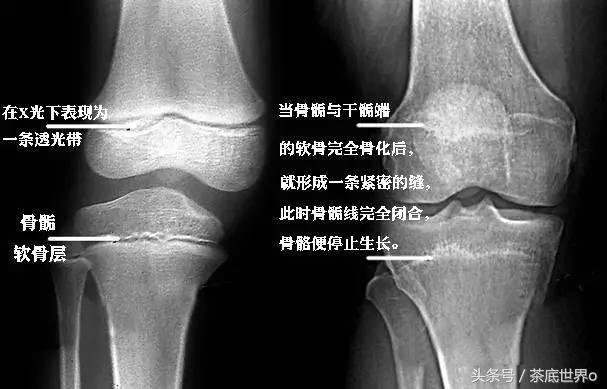

一般来说,只要男生的骨骺线还处于未闭合状态,就一直处于还能长高的状态。

具体还能不能长高可以到医院照个X光,看看自己的骨垢线是否闭合,男生过了18岁就不再长高,这种说法是不靠谱的,有人结了婚还能窜一窜呢!